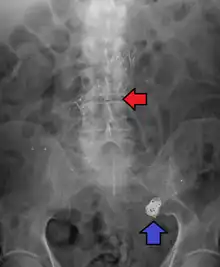

Abdominal aortic aneurysms are commonly divided according to their size and symptomatology. An aneurysm is usually defined as an outer aortic diameter over 3 cm (normal diameter of the aorta is around 2 cm),[37] or more than 50% of normal diameter that of a healthy individual of the same sex and age.[10][38] If the outer diameter exceeds 5.5 cm, the aneurysm is considered to be large.[36]

The common iliac artery is classified as:[39]

| Normal | Diameter ≤12 mm |

| Ectatic | Diameter 12 to 18 mm |

| Aneurysm | Diameter ≥18 mm |